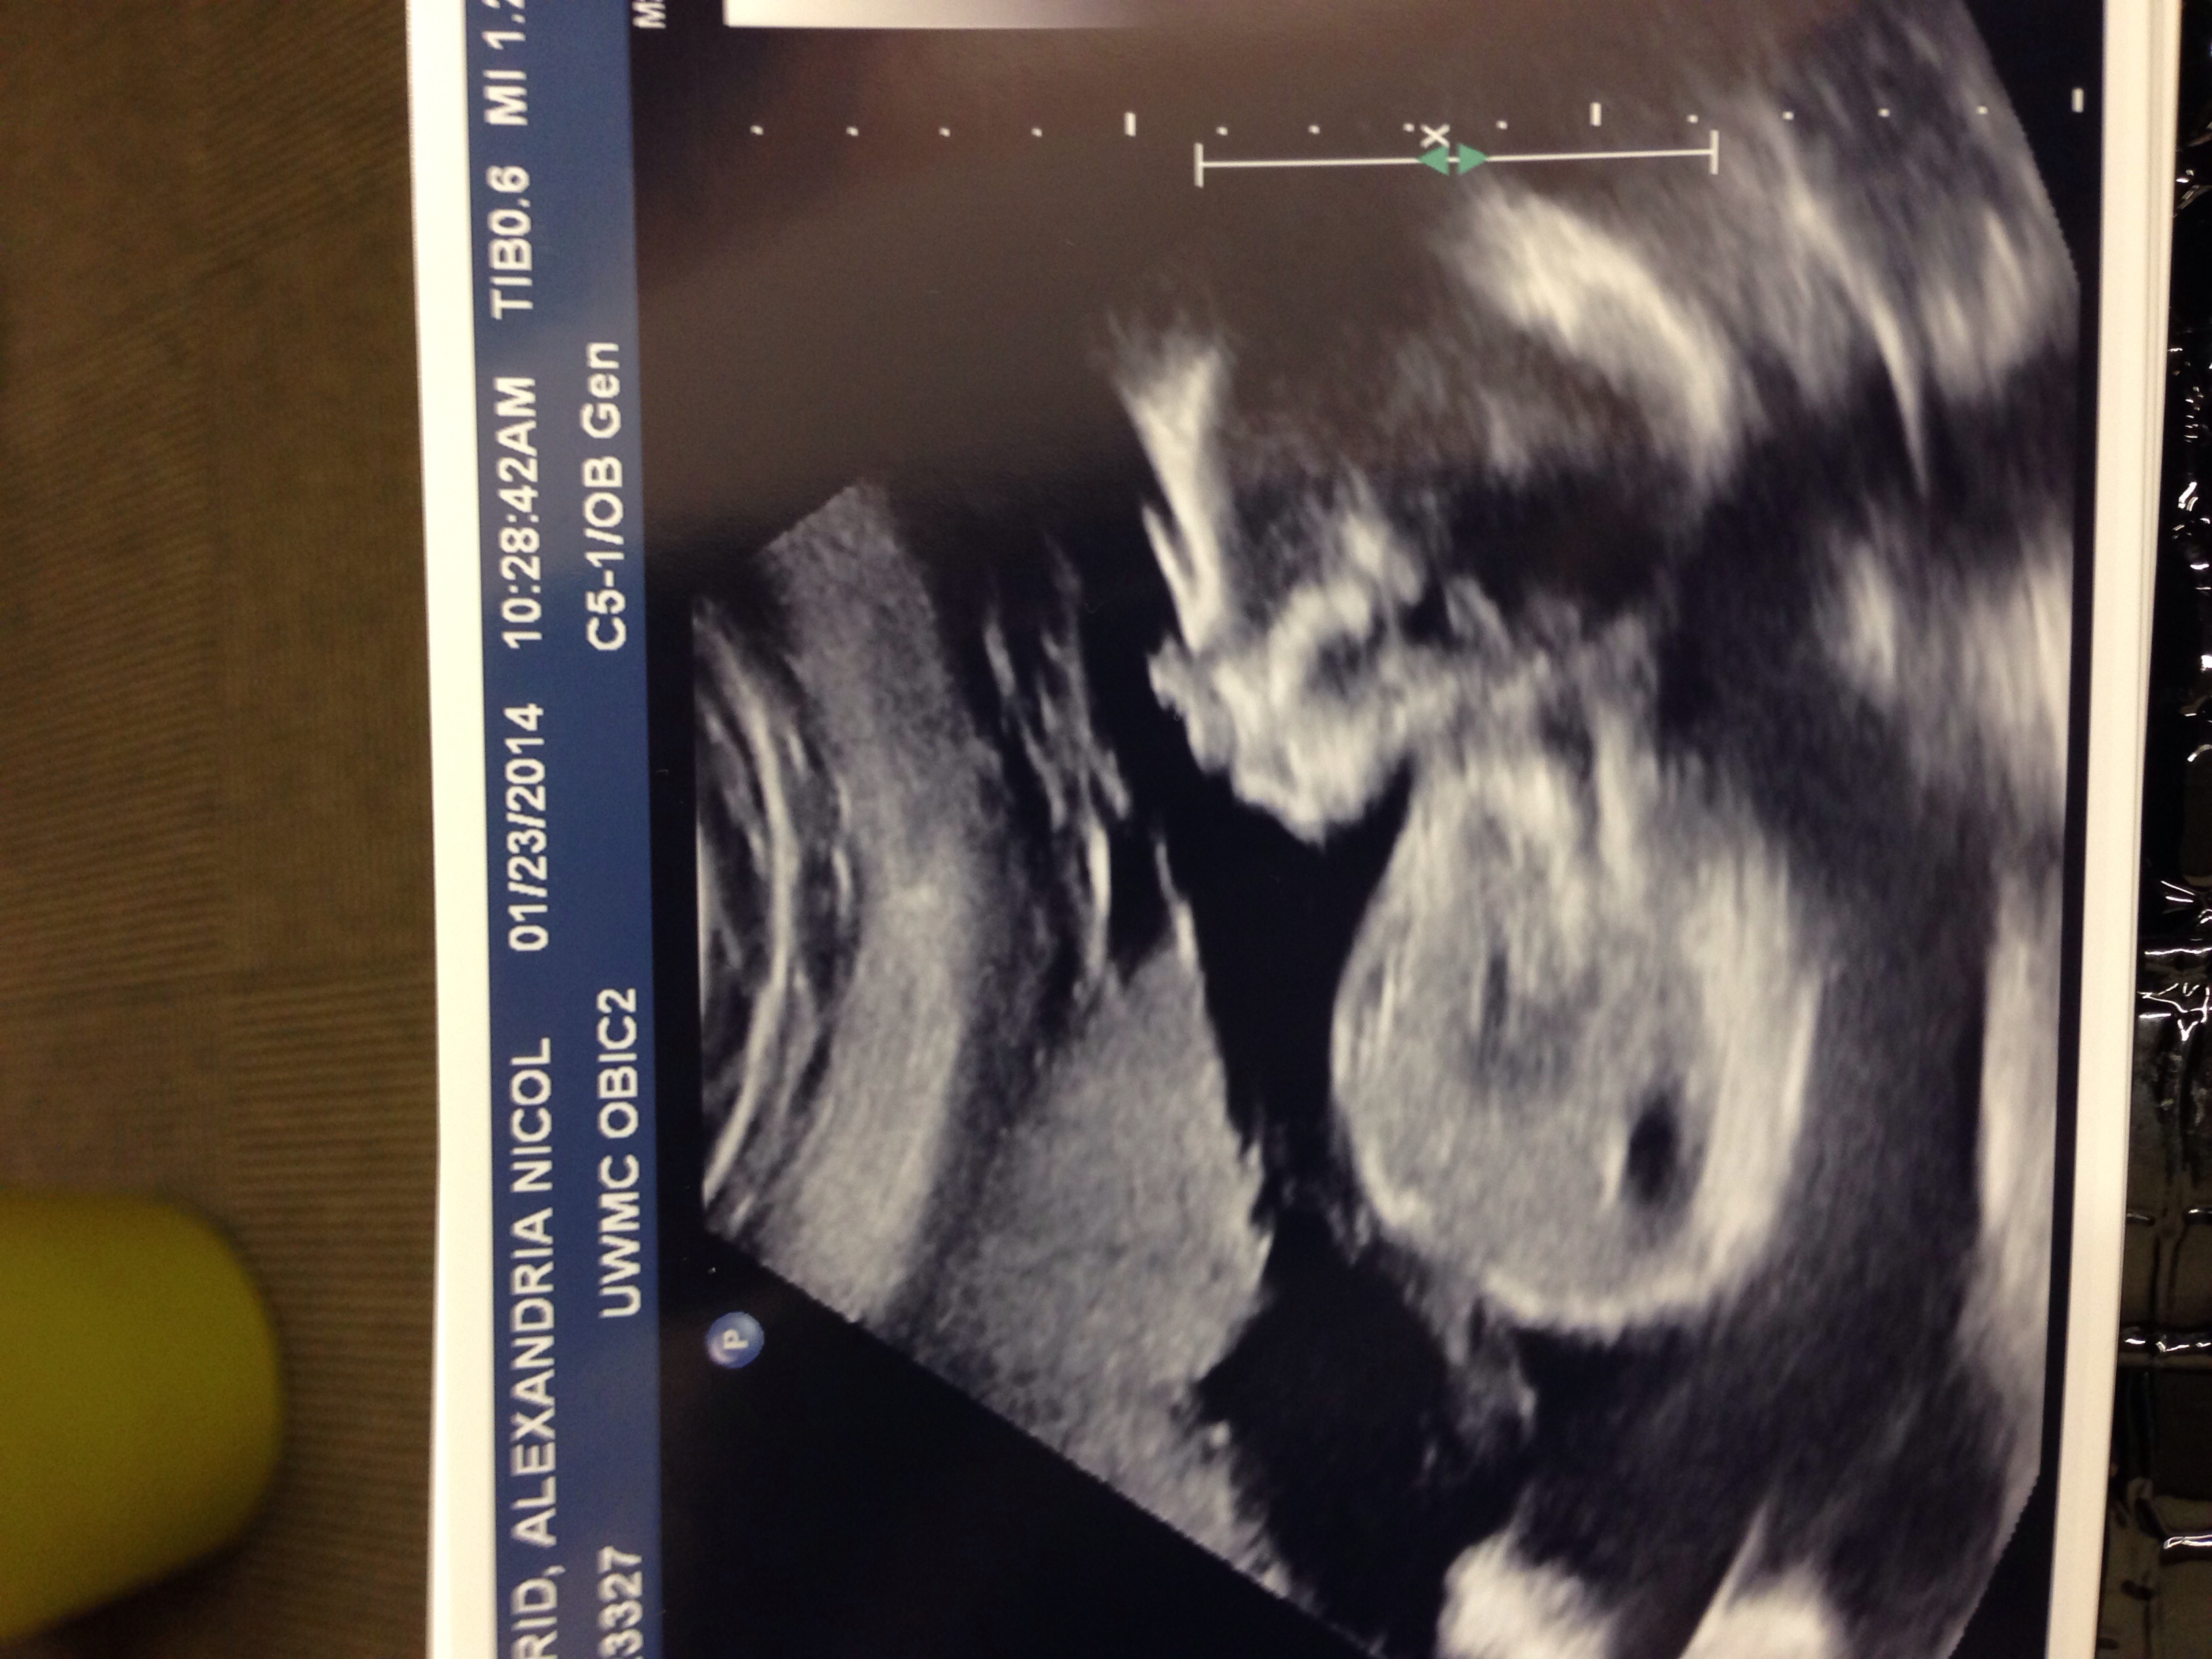

We had our anatomy scan this morning bright and early. Measuring 3 days ahead with all parts that are supposed to be there and appearing to be a very healthy baby!

We also turned into Team Blue and have lots of photos to stare at until our next U/S @ 28 weeks. Every old wives tale there is was wrong with me... there goes that!

Baby looks great! She's still a stubborn little thing and it took a while to cooperate but there are no issues with her heart and we were reassured (for a 3rd time) that there is a girl in there!